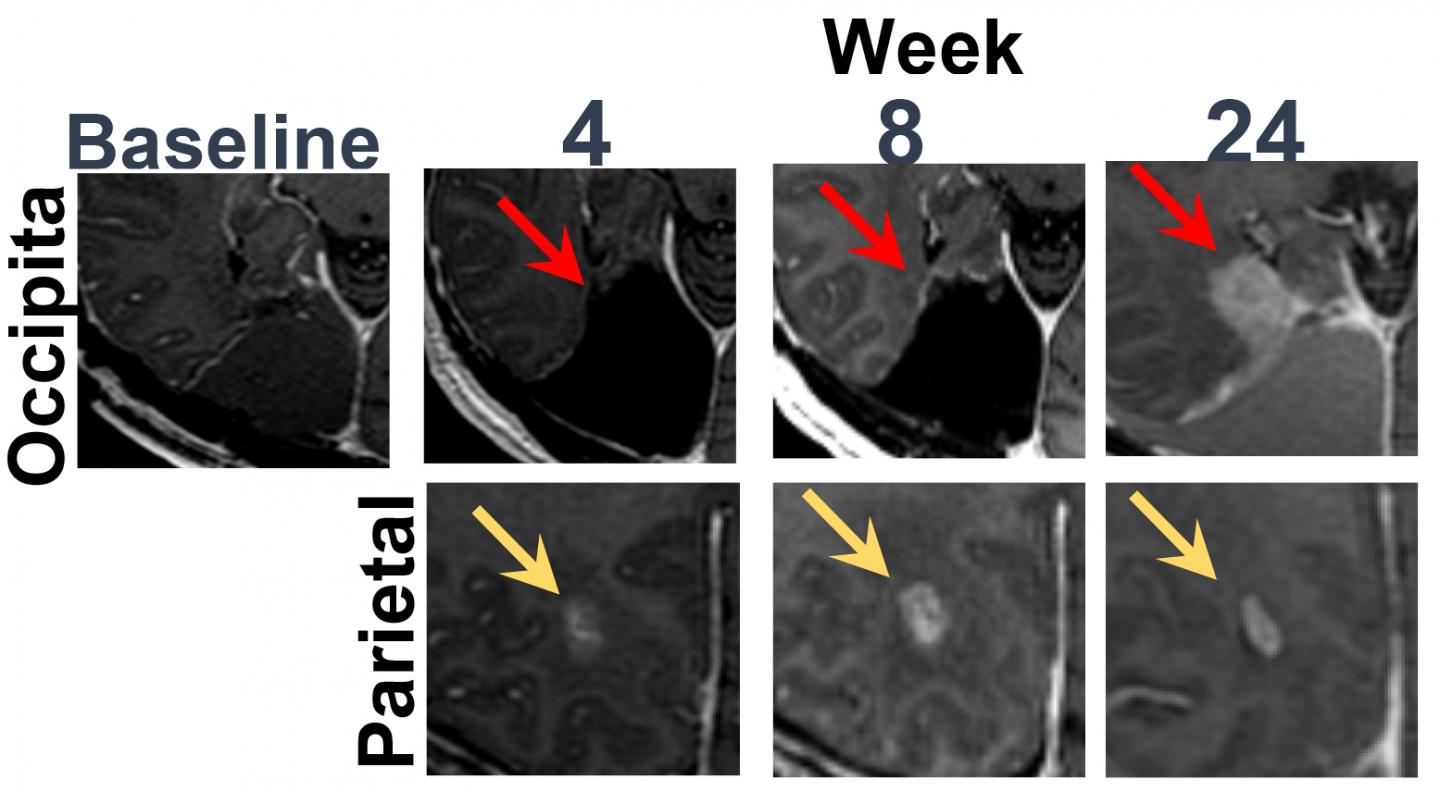

From cds.ismrm.org